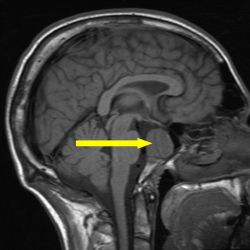

Микроаденома гипофиза - это доброкачественная опухоль в небольшой железе у основания головного мозга. Заболевание может появиться в любом возрасте, но чаще встречается у пожилых людей. Поскольку опухоль может провоцировать серьезные проблемы со здоровьем, ее следует лечить.